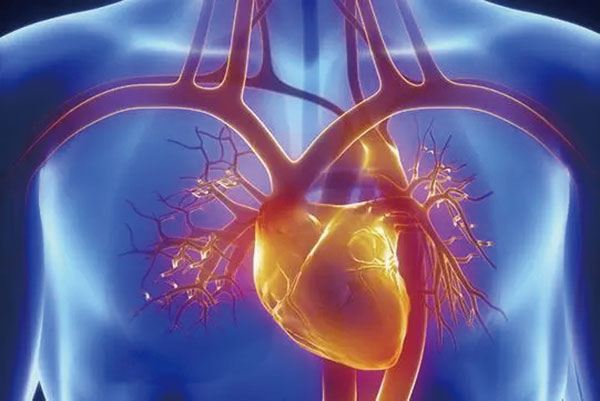

5、心脏——排除冠心病用CT,看心功能用超声

常规的心脏结构与功能检查,心脏彩超所提供的信息已经较为充分,又简单易行。

用CT可检查冠状动脉,但冠脉CT检查辐射量较大,不适合作为常规体检。核磁虽无电磁辐射,但对冠状动脉的观察不及CT。心脏核磁则是评价心脏结构和功能的"金标准"。